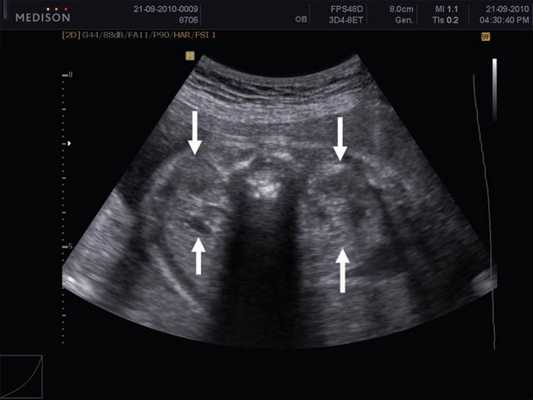

Результаты исследования: размеры плода пропорциональные, соответствуют менструальному сроку беременности. При эхокардиографии особенностей строения сердца у плода не выявлено. При оценке органов мочевыделительной системы обнаружено следующее: правая почка плода нормальных размеров и структуры. Левая почка увеличена до размеров 53х38х46 мм при 95-м процентиле нормативных для срока значений 43х24х23 мм [4] (рис. 1). В структуре почки, преимущественно в верхнем и среднем сегментах, определяется округлое образование без четких контуров, средней эхогенности, приблизительные размеры его 50х35х35 мм. При цветовом допплеровском картировании в образовании визуализируется обширная сосудистая сеть. При допплерометрии индексы сосудистой резистентности (рис. 2) в разных участках образования варьируют в широких пределах (от 0,49 до 0,77).

Рис. 1. Почки плода в режиме 2D. Видна разница в эхографической структуре. Границы почек обозначены стрелками.

При ультразвуковом исследовании в пренатальном периоде опухоль определяется как округлое образование, как правило, больших размеров, без четких контуров. Разница в акустической плотности интактной почечной паренхимы и опухолевой ткани может создавать эффект границы, которая глазом будет восприниматься как капсула. В большинстве случаев при беременности, осложненной возникновением мезобластической нефромы, регистрируется многоводие. Сочетанные изменения в других органах и системах плода встречаются редко.

В представленном клиническом наблюдении диагноз опухоли почки был поставлен нами практически сразу и не вызывал сомнения, поскольку стандартный протокол ультразвукового скринингового исследования во II и III триместрах беременности требует описания почек и мочевого пузыря. Почки оцениваются в поперечном и продольном сечениях с использованием при необходимости цветового допплеровского картирования (рис. 3, а, б). В данном случае почки плода располагались в типичном месте, но обращали на себя внимание значительная разница в размерах и необычная структура одной из почек (см. рис. 1). В 2D режиме границы опухоли четко не визуализировались, но при использовании технологии VCI (объемное контрастное изображение) можно было более точно определить ее контуры (рис. 4).